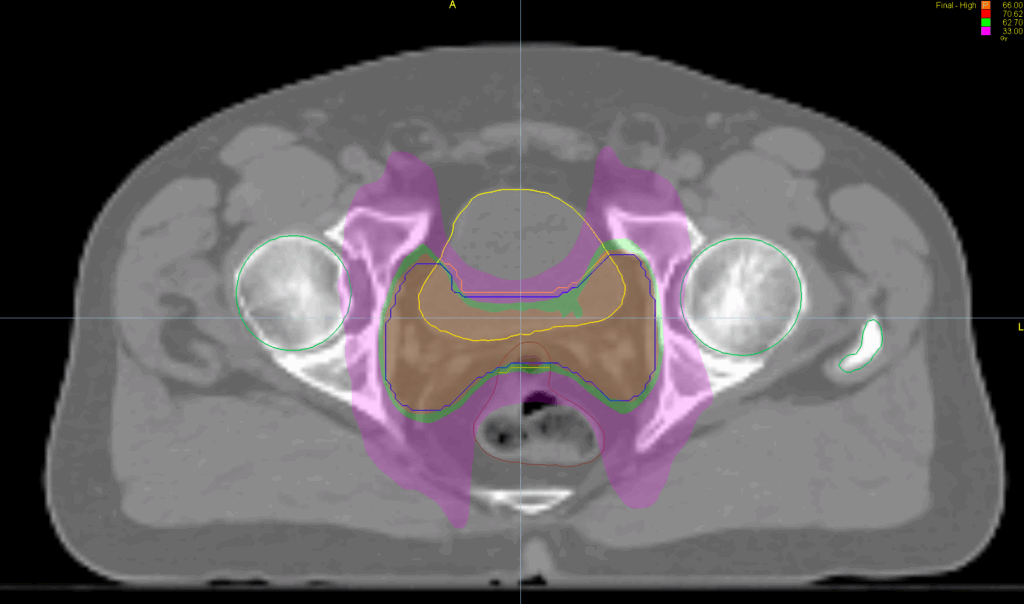

Treatment Plan Images

Fractionation / Protocol Used

66 Gy in 33 fractions

PTV(s) Volume, Length

165 cc, 6.8 cm